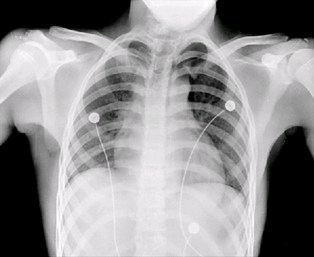

(2)二维信号f(x,y)有:图像:普通照片,遥感图像,工业图像,医学图像等。

人体胸部X射线图像